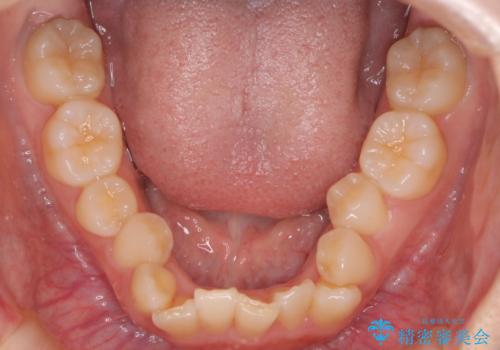

ディープバイト改善のためのインビザライン治療

- 患者様は、全体的な歯列のガタガタとディープバイト(深い噛み合わせ)を主訴として来院されました。診断の結果、ディープバイトを改善するためには、歯列全体の拡大が必要であると判断しました。治療には、透明なマウスピース型矯正装置「インビザライン」を使用し、歯を適切に拡大しながら歯並びを整える計画を立てました。治療期間はおおよそ2年を見込んで進め、最終的に見た目にも大きく変化をもたらすことを目指しました。

ディープバイトの治療には、奥歯の高さや前歯の位置に対する繊細な調整が必要です。本症例では、インビザラインによる歯列拡大を行うことで、噛み合わせを改善し、歯並び全体を整えました。治療過程では、歯間のスペースを確保するため、IPR(インタープロキシマルリダクション)を適宜行い、無理なく歯列の調整を行いました。治療後は、歯並びが大きく改善され、患者様の見た目にも大きな変化が現れました。インビザラインは透明で目立たず、治療中の見た目を気にされる患者様にも配慮した治療法です。